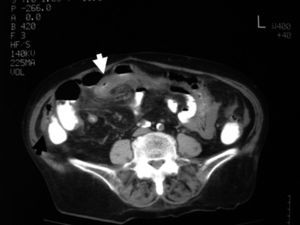

Debido a la clínica inespecífica, los estudios de imagen son fundamentales para el diagnóstico1,5, especialmente en los períodos sintomáticos. La tomografía computarizada (TC) es de elección en la evaluación y el tratamiento de los pacientes con obstrucción intestinal, ya que permite confirmar el diagnóstico, identificar su causa y evidenciar los signos de isquemia, que requieren una pronta intervención. Los criterios radiológicos compatibles con hernias pericecales incarceradas incluyen agrupación de asas de intestino delgado dilatadas llenas de líquido, a veces encapsuladas, que se localizan entre la pared abdominal y el ciego, al que desplazan anteromedialmente; los vasos mesentéricos están ingurgitados, elongados y convergen hacia el saco6–8.

Las pruebas complementarias realizadas al ingreso son hemograma (hemoglobina de 11,1g/dl; hematocrito de 34%, y conteo de leucocitos de 8.63/l, con fórmula normal) y bioquímica (glucemia de 110mg/dl; creatinina de 1,4mg/dl; amilasa de 22U/l; sodio de 139mEq/l; potasio de 3,9mEq/l, proteína C reactiva de 125U). En la radiografía de tórax se observa derrame pleural derecho, sin neumoperitoneo. En la radiografía de abdomen se observa distensión moderada de asas de intestino delgado y aire visible en el colon, que es de diámetro normal. En la TC abdominal se visualiza engrosamiento segmentario de un asa del intestino delgado con discreta dilatación del asa proximal a ésta, que en el estudio sin contraste se encuentra localizada en la gotiera derecha, con desplazamiento anterior y medial del ciego, con los vasos mesentéricos elongados y dirigidos hacia esa asa (fig. 1). Tras la administración de contraste oral, esa asa se desplaza hacia el mesogastrio, con cambio de orientación de los vasos mesentéricos; el engrosamiento segmentario y concéntrico de la pared persiste (fig. 2). Hay una pequeña cantidad de líquido libre en ambas gotieras y pelvis.